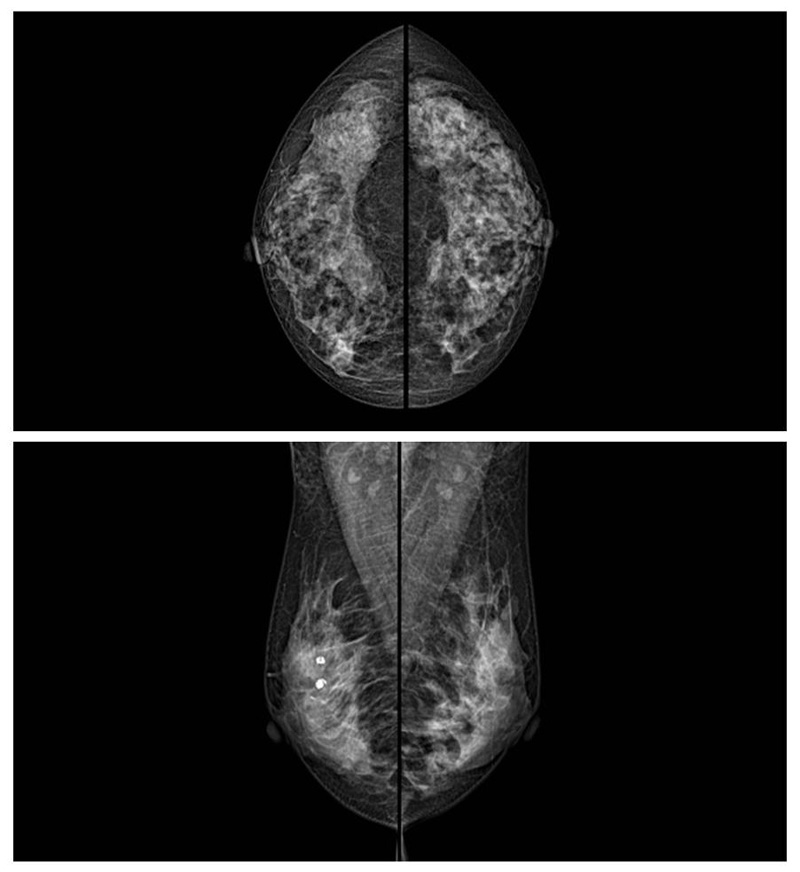

如何使用乳腺DR来拍摄乳房检查

乳腺癌的发生率越来越高,已经是我们国家的癌症之一已成为女性健康“头号杀手”。乳腺DR可提高乳腺癌早期检出率并精准定位。发现和诊断早期乳腺癌最有效的方法之一,明显利大于弊女性都要重视乳腺的检查。辐射很小最简便、最可靠、无创性检查手段,做一次乳腺DR的剂量相当于7周的正常生活。尤其是对于40岁以上的女性尤为重要,那么乳腺DR是怎么进行检查的呢?我们来了解一下,为广大朋友在检查前有点心理准备。检查时候是避开经期的前后,月经来后的7天左右比较合适。需要脱衣服检查,根据拍片的摆位要求,有头尾位置,内外斜位,还有侧位。定点放大压迫方法可以更细微清晰的检查出病灶。

对乳房进行按压,这样才能得到检查的好效果,按压大概60秒左右,做好心理准备不可以过度紧张有点疼痛感觉,这样不会抖动影响了检查的效果。减少患者压迫时间和辐射剂量??纱锏阶罡呒薹直媛?0.1 lp/mm,可实现高清成像,提高微小病变检出率??梢苑⑾秩橄僭錾髦至级裥灾讖A通过三维断层扫描,提高乳腺微小癌灶的检出率和早期乳腺疾病特别是乳腺癌的诊断率。通过特殊的支架,加大胶片与物体之间的距离来获取更多的影像信息。